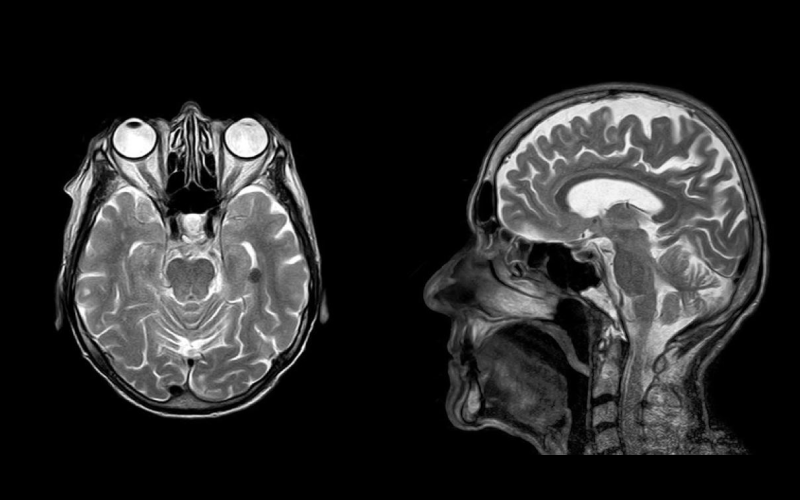

Un nuevo malware de escáner tomográfico y resonancia magnética es capaz de modificar los resultados, haciendo creer a los médicos que tenemos cáncer.

Los escáneres de tomografía y de imagen por resonancia magnética son valiosas herramientas para comprender mejor el interior de nuestro cuerpo. Ofrecen grandes ventajas respecto a un escáner de rayos X convencional. Como la posibilidad de obtener imágenes en todos los ángulos posibles en el caso de las tomografías; o la de obtener imágenes secuenciales en secciones del cuerpo en el caso de la resonancia magnética.

Estas imágenes son muy útiles, especialmente para descubrir tumores cancerígenos. Pueden ser vitales para comprender mejor la localización y el alcance del cáncer, para conseguir el mejor diagnóstico y por lo tanto, el tratamiento adecuado. Aunque a veces es normal encontrarse con artefactos visuales en estas pruebas (sobre todo si el paciente se ha movido), suelen ser bastante fiables.